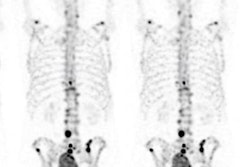

SPECT/CT imaging is an effective way to evaluate noninfected painful knees in patients after they have undergone arthroplasty, a literature review published on 21 March in the Journal of Orthopaedic Surgery and Research has found.

A team of nuclear medicine physicians and orthopedic surgeons led by Dr. Kelly Anzola, PhD, of the Clinica Reina Sofia in Bogota, Colombia, found that SPECT/CT proved highly accurate for identifying different sources of knee pain, particularly in cases of joint loosening, patellofemoral disorders, and component malalignment.

The review indicated that for cases of loosening, patellofemoral disorders, and component malalignment -- all of which can be significant causes of pain after arthroplasty -- SPECT/CT's sensitivity and specificity were 86% and 90%.